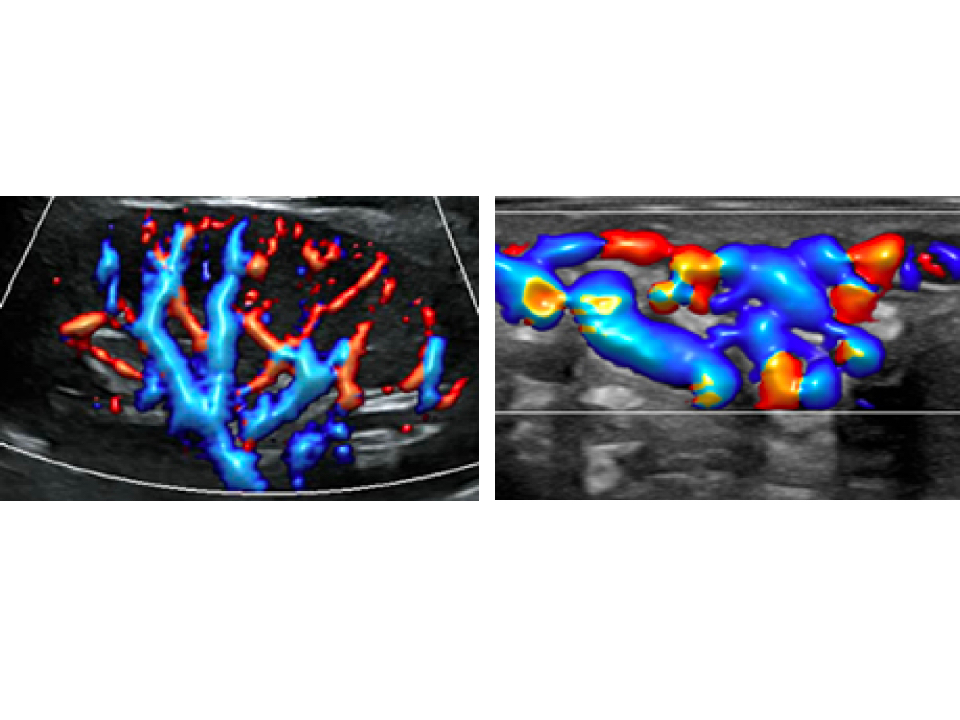

Smart Track

ItŌĆÖs Mindray unique feature to reduce repetitive, time-consuming scanning steps in vascular exams. Smart Track provides intelligent and real-time vessel tracking and real-time image optimization of Color and PW.

?